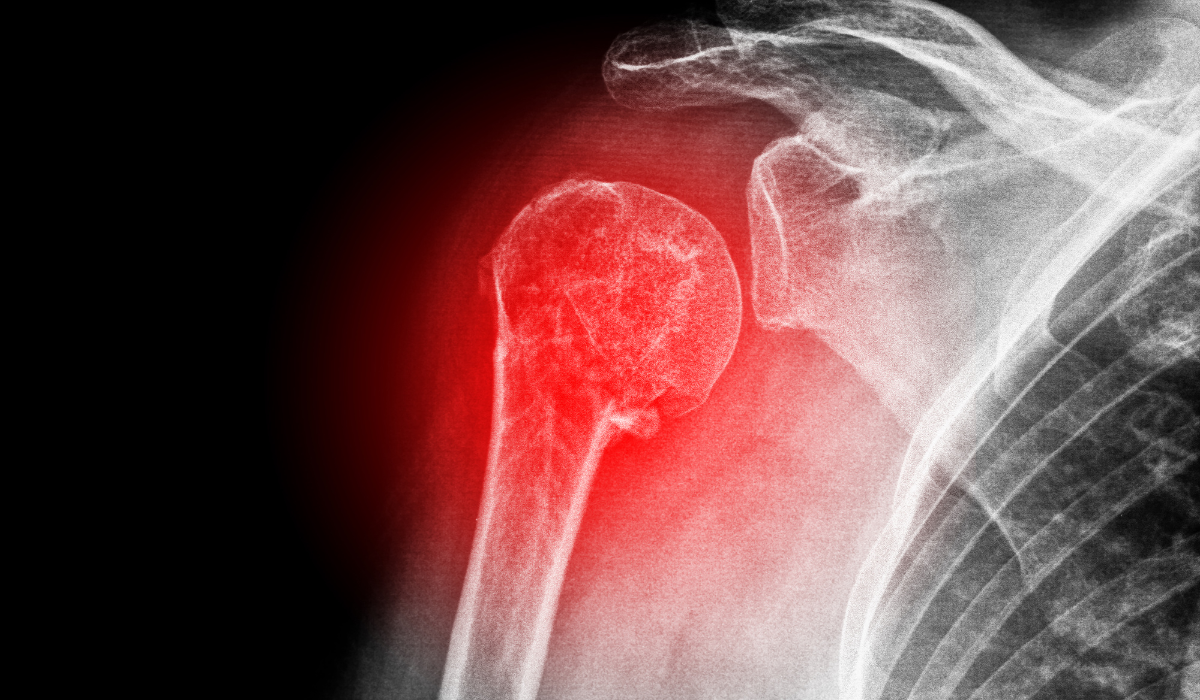

In a few sufferers the ball (humeral head) comes out of the socket (glenoid), a circumstance known as dislocation. It is related to extreme ache and the incapacity to transport the shoulder. It can also additionally take place because of damage to the shoulder in the course of falls, avenue visitors accidents, or at the same time as gambling sports activities.

This circumstance normally influences more youthful humans and those sufferers prevent all wearing sports and different high-calls for jobs as they increase a worry of repeated dislocations. In lots of those sufferers, this circumstance can efficiently be handled with key-hole (arthroscopic) surgical procedure.

The maximum not unusual place reasons of shoulder dislocations consist of: Sports accidents Accidents, which includes visitors accidents Falling to your shoulder or outstretched arm Seizures and electric powered shocks.